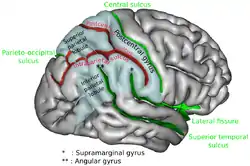

Position of angular gyrus (shown in red).

Position of angular gyrus (shown in red). Lateral surface of left cerebral hemisphere, viewed from above. Angular gyrus is shown in orange.